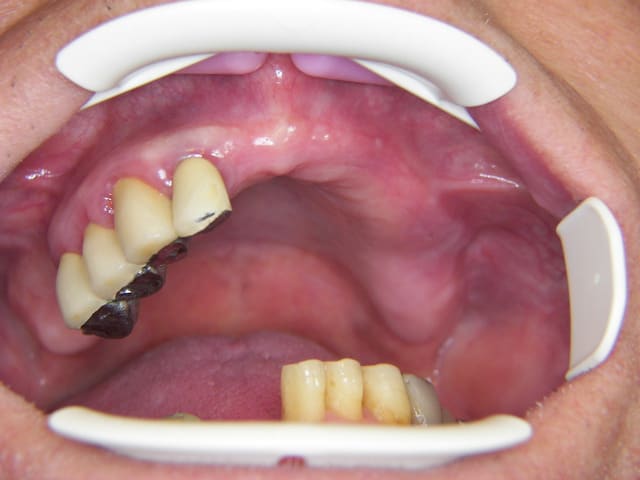

photos de la bouche au départ

100 4442r ro8hie - Eugenol

100 4473r hvl501 - Eugenol

100 4446 o2upvt - Eugenol